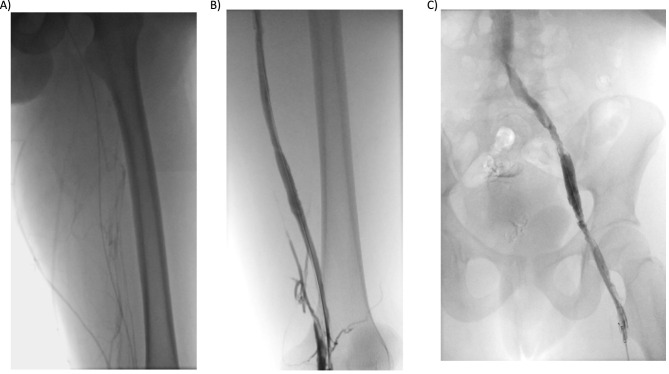

Combined thrombophilia represents 7.8-8.3% of the patients with thrombophilia and confers a higher risk for thrombosis development and recurrence. Here, we present a 17-year-old boy carrier of three congenital thrombophilias, two severe (type I antithrombin deficiency and type I protein S deficiency) and one prothrombotic polymorphism (prothrombin G20210A), all in heterozygosis. He developed an extensive deep venous thrombosis in lower left limb, reaching proximal inferior vena cava and contralateral iliac vein, in the setting of prolonged rest. Endovascular therapy with local thrombolytic agent infusion followed by mechanical thrombectomy was performed, achieving a favorable clinical and radiological evolution. Antithrombin replacement to achieve levels between 80% and 120% with heparin administration was used during the endovascular procedure. The patient is currently asymptomatic and maintains indefinite anticoagulation with warfarin, keeping an appropriate anticoagulation range (international normalized range between 2.5 and 3.5).

合并血栓性疾病患者占血栓性疾病患者的 7.8%-8.3%,血栓形成和复发的风险较高。这里,我们要介绍的是一名 17 岁男孩,他患有三种先天性血栓性疾病,其中两种为重度(I 型抗凝血酶缺乏症和 I 型蛋白 S 缺乏症),一种为凝血酶原多态性(凝血酶原 G20210A),均为杂合型。在长时间休息的情况下,他的左下肢出现了广泛的深静脉血栓,血栓到达下腔静脉近端和对侧髂静脉。患者接受了局部溶栓的血管内治疗,随后进行了机械性血栓切除术,临床和影像学结果良好。在血管内治疗过程中,使用了抗凝血酶替代物,使肝素水平达到 80% 至 120%。患者目前没有任何症状,仍在使用华法林进行无限期抗凝,并保持适当的抗凝范围(国际正常化范围在 2.5 至 3.5 之间)。